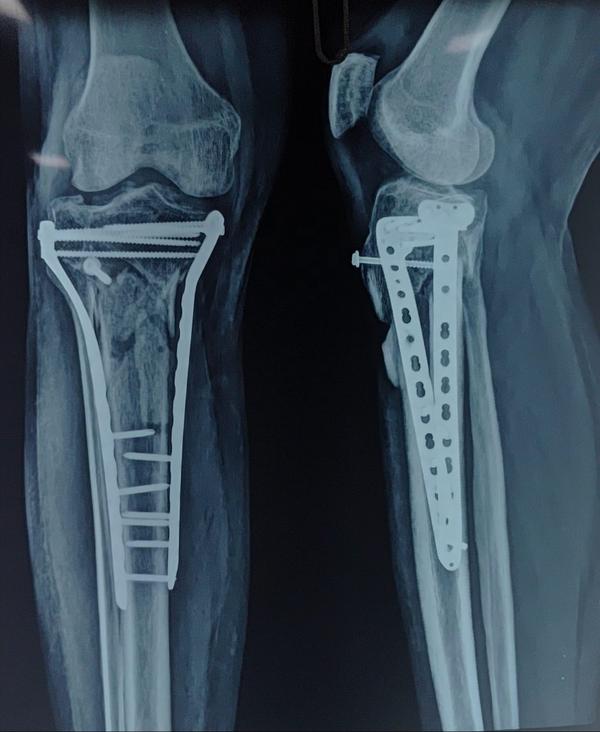

Type 6 Schatzker Tibial Condyle fracture 4 months post op .Patient walking full weight bearing.